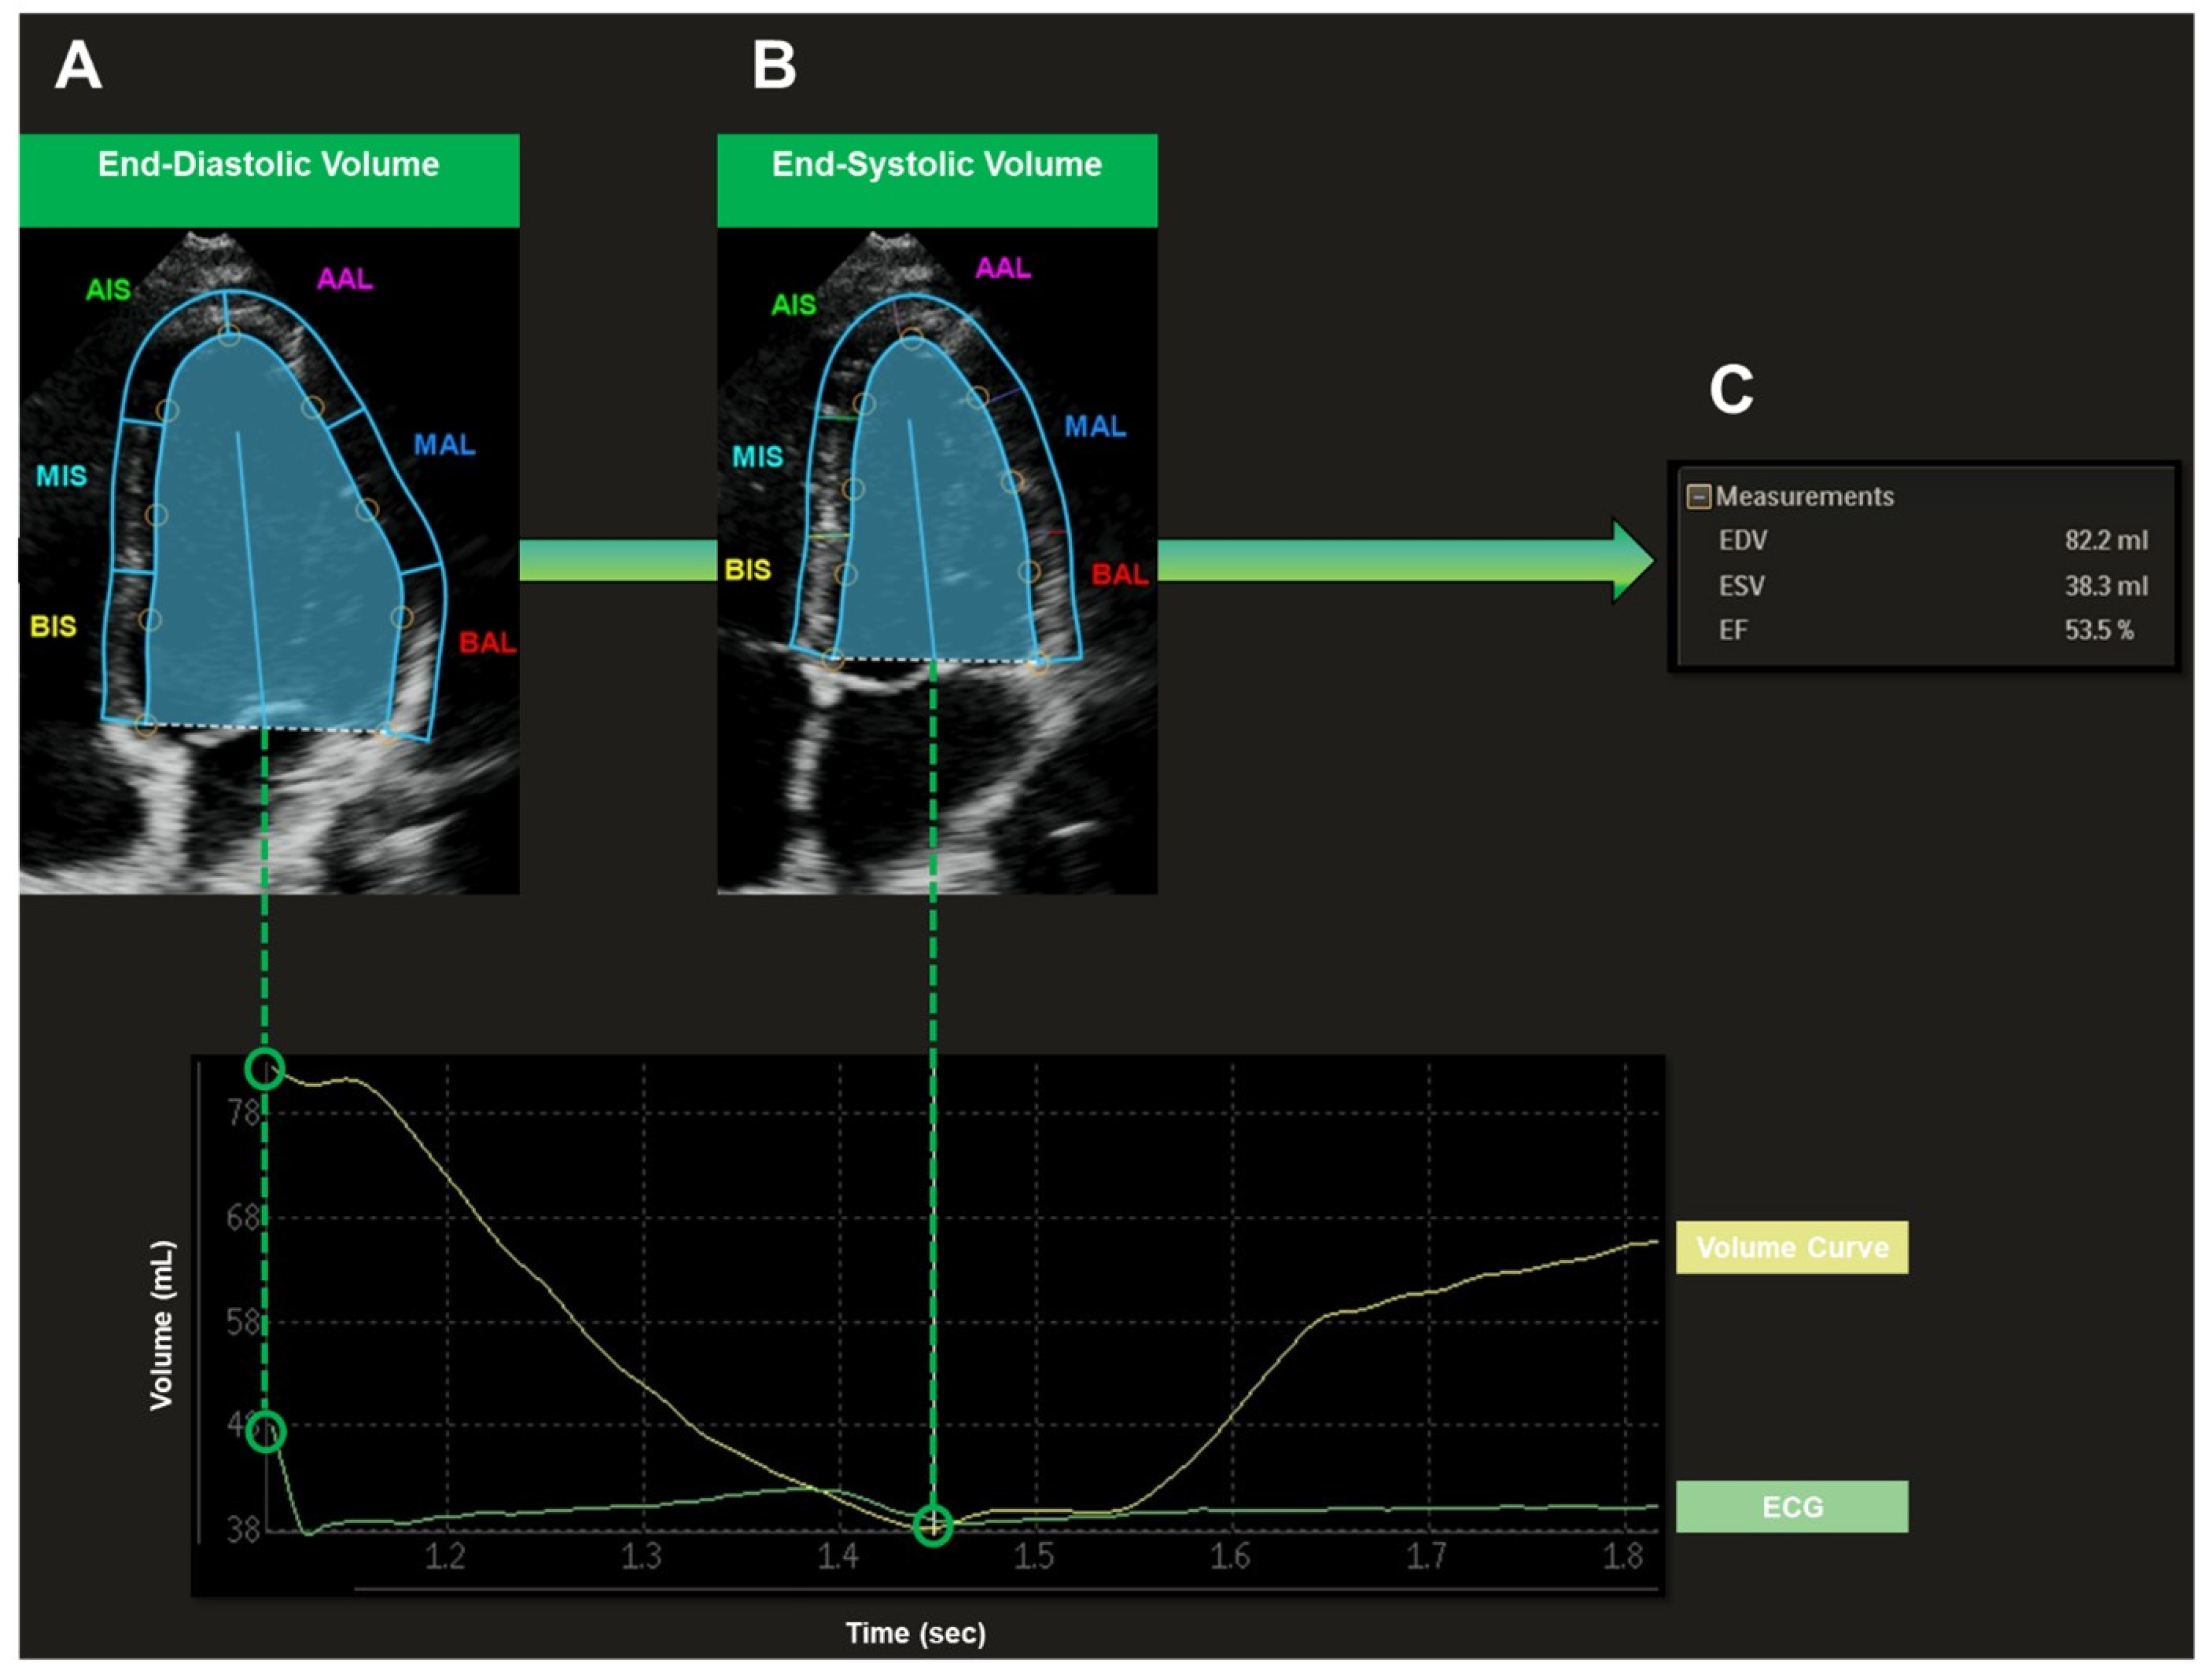

For the LV echocardiographic examination, a Philips iE33 xMatrix or a Philips Epiq 7G ultrasound device (Philips Healthcare, Amsterdam, The Netherlands) was used. A 1–5 MHz or a 3–8 MHz sector ultrasound transducer (Philips Healthcare, Amsterdam, The Netherlands) was utilized. The LV was recorded in apical four-chamber view under three-lead ECG tracking. Four consecutive loops were acquired. Special care was taken to portray the entire LV cavity. Recorded loops were transferred to a separate workstation (QLAB cardiovascular ultrasound quantification software, version 11.1, Philips Healthcare, Amsterdam, The Netherlands) for further analysis (Figure 1). End-diastole (R wave in ECG) and end-systole (end of T wave in ECG) were set automatically by the software. The LV endocardium was marked precisely by the investigator in the end-diastole and end-systole. The following parameters were then acquired semiautomatically by the software: LV end-diastolic volume (EDV, mL), LV end-systolic volume (ESV, mL), LV stroke volume (SV, mL), LV ejection fraction (EF, %).

Figure 1.

Semiautomatic Assessment of Left Ventricular Volumes Recorded in Apical Four-Chamber View. End-diastole (A) (R wave in ECG) and end-systole (B) (end of T wave in ECG) were set automatically by the software. The LV endocardium was marked precisely by the investigator in end-diastole (A) and end-systole (B). The following parameters were then acquired semiautomatically by the software (C): EDV, end-diastolic volume; ESV, end-systolic volume; SV, stroke volume; EF, ejection fraction.